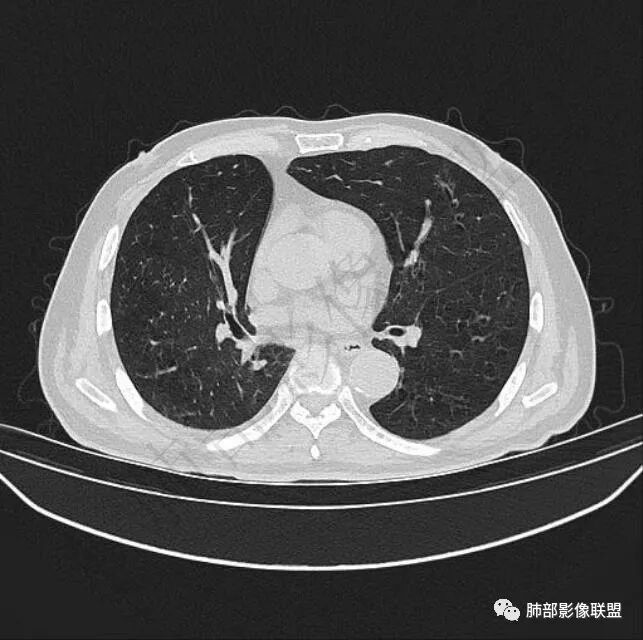

二..发现左肺上叶舌段实性密度小结节影,不规则略呈半环形,边界清楚,未见分叶、毛刺及磨玻璃晕。未见卫星病灶。

9个月后病灶明显增大,边缘较平直,部分膨隆,锁扣样外观,仍旧缺乏典型深分叶及张力,未见胸膜凹陷。

再1个多月后病灶继续增大,较明显不均匀强化,肺门一侧见低密度区。病灶边缘相对不清,可见毛刺。